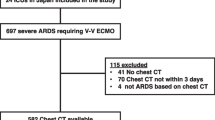

Between September 2015 and April 2022, twenty-two patients who underwent VA-ECMO support and LUS measurement and with cardiogenic shock were enrolled in the study. Eleven patients had acute myocardial infarction, 8 had fulminant myocarditis, and 3 had heart failure after cardiac surgery. The patients were divided into survivors (n = 16) and nonsurvivors (n = 6).

Twenty-two patients with refractory cardiogenic shock who received VA-ECMO support in our centre were included in the study, including 13 males and 9 females aged 14 to 77 years. There were 11 cases of acute myocardial infarction, 8 cases of fulminant myocarditis and 3 cases of cardiac postoperative assistance. All patients received endotracheal intubation and ventilator-assisted breathing.

According to discharge survival status, the patients were divided into a survival group (n = 16) and a nonsurvivor group (n = 6). There were no significant differences with regard to age, sex, basic diseases, APACHE II, ECMO running time, or mechanical ventilation support time between the two groups (all P > 0.05). However, the length of ICU stay in the survival group was longer than that in the nonsurvivor group (P < 0.05). Detailed baseline characteristics for the study population are shown in Table 1.